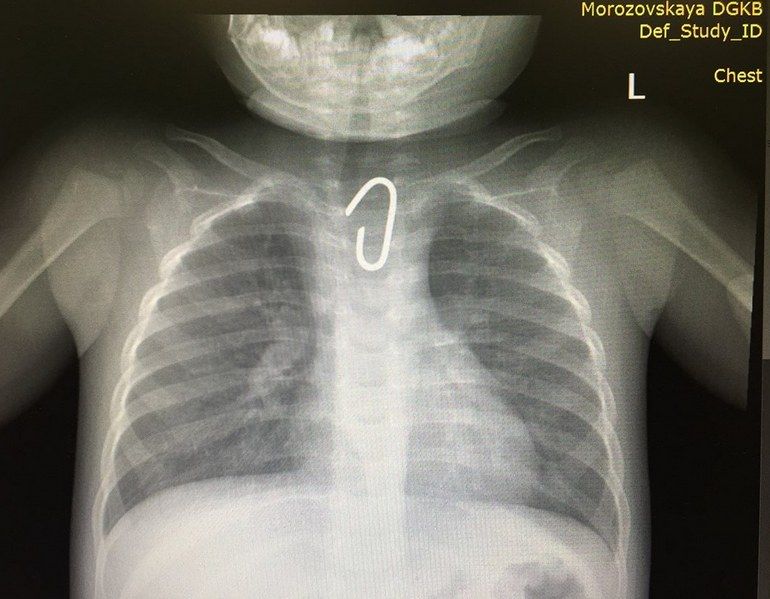

При поступлении проведено рентгенологическое исследование.

Снимок показал, что причиной затруднения дыхания являлось инородное тело сложной конфигурации, похожее на изогнутый кусок толстой проволоки (диаметром около 1 мм), с двумя острыми концами, находящимися в верхнем отделе пищевода.